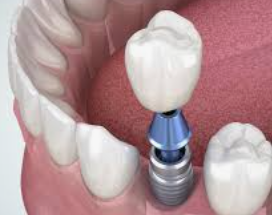

2단계 - 수술: 치과 의사는 어금니 부위에 조심스럽게 구멍을 내고 임플란트를 삽입합니다. 그 후, 임플란트 주위의 뼈와 임플란트가 안정적으로 결합되도록 치유를 위한 기간을 마련합니다. 이 과정은 일반적으로 수 주에서 몇 개월까지 소요될 수 있습니다.

3단계 - 임시 크라운 부착: 치유 기간 이후, 임플란트와 주변 뼈가 충분히 결합된 것으로 판단되면 임시 크라운을 임플란트에 부착합니다. 이를 통해 환자는 정상적인 식사와 말하기를 할 수 있게 됩니다.

4단계 - 영구 크라운 설치: 뼈와 임플란트가 완전히 결합된 후, 임시 크라운을 제거하고 영구 크라운을 설치합니다. 이 단계에서는 어금니의 자연스러운 외관과 느낌을 제공하여 장기적으로 안정성과 기능성을 보장합니다.